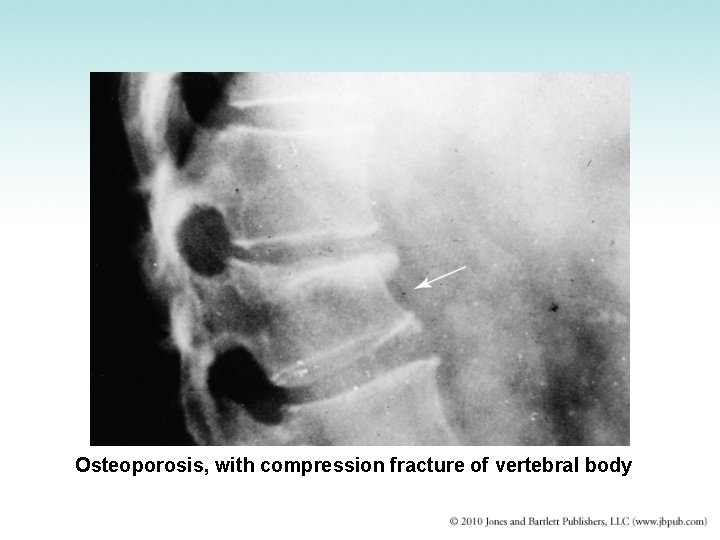

Osteoporosis with a compression fracture of vertebral body.

Osteoporosis • Generalized thinning and demineralization of entire skeletal system – “Porous bones” – Most common in postmenopausal women – Loss of estrogen accelerates rate of bone resorption – Also develops in elderly men • Treatment: high-calcium diet, estrogen

Osteoporosis, with compression fracture of vertebral body